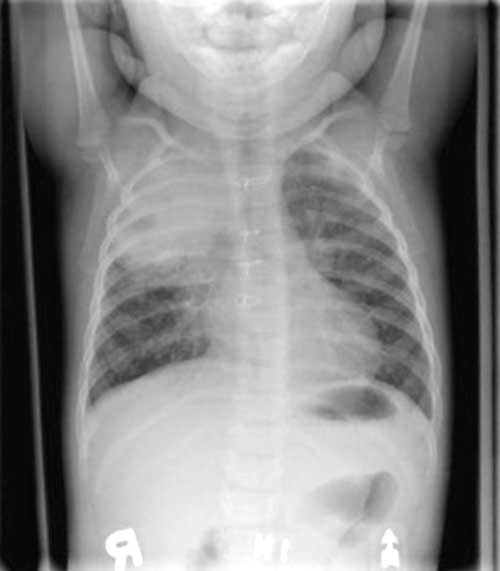

The

CHEST X-RAY is seen below.

Enlarge this CHEST

X-RAY (LEFT). Enlarge this CHEST

X-RAY (RIGHT)

WHAT IS YOUR INTERPRETATION?